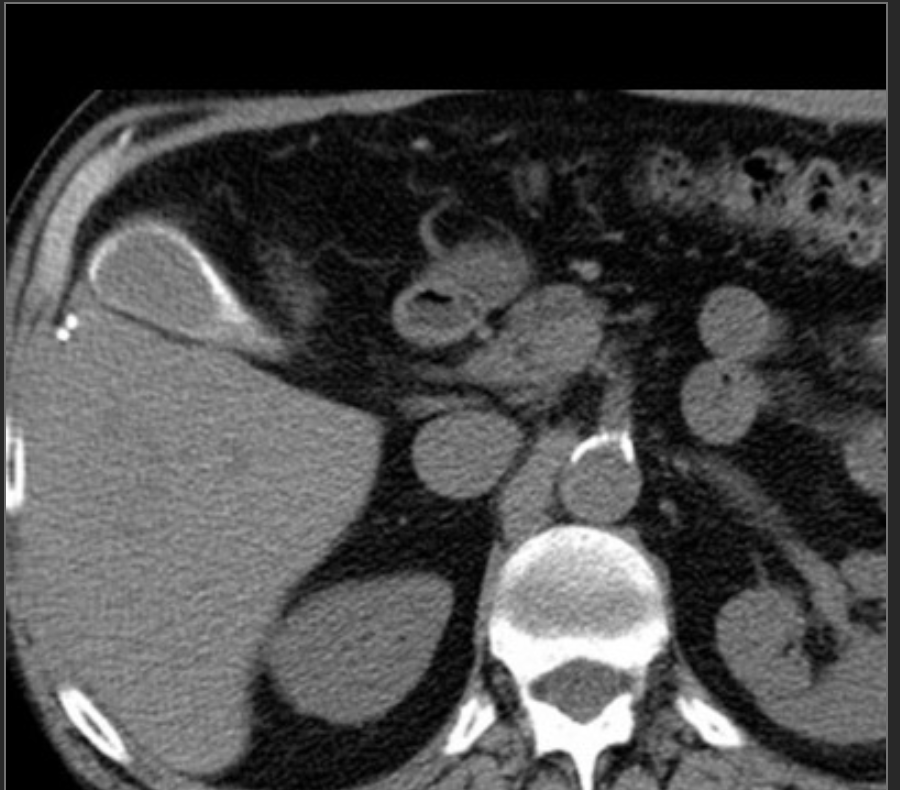

Dx?

Dx: gangrenous chole.